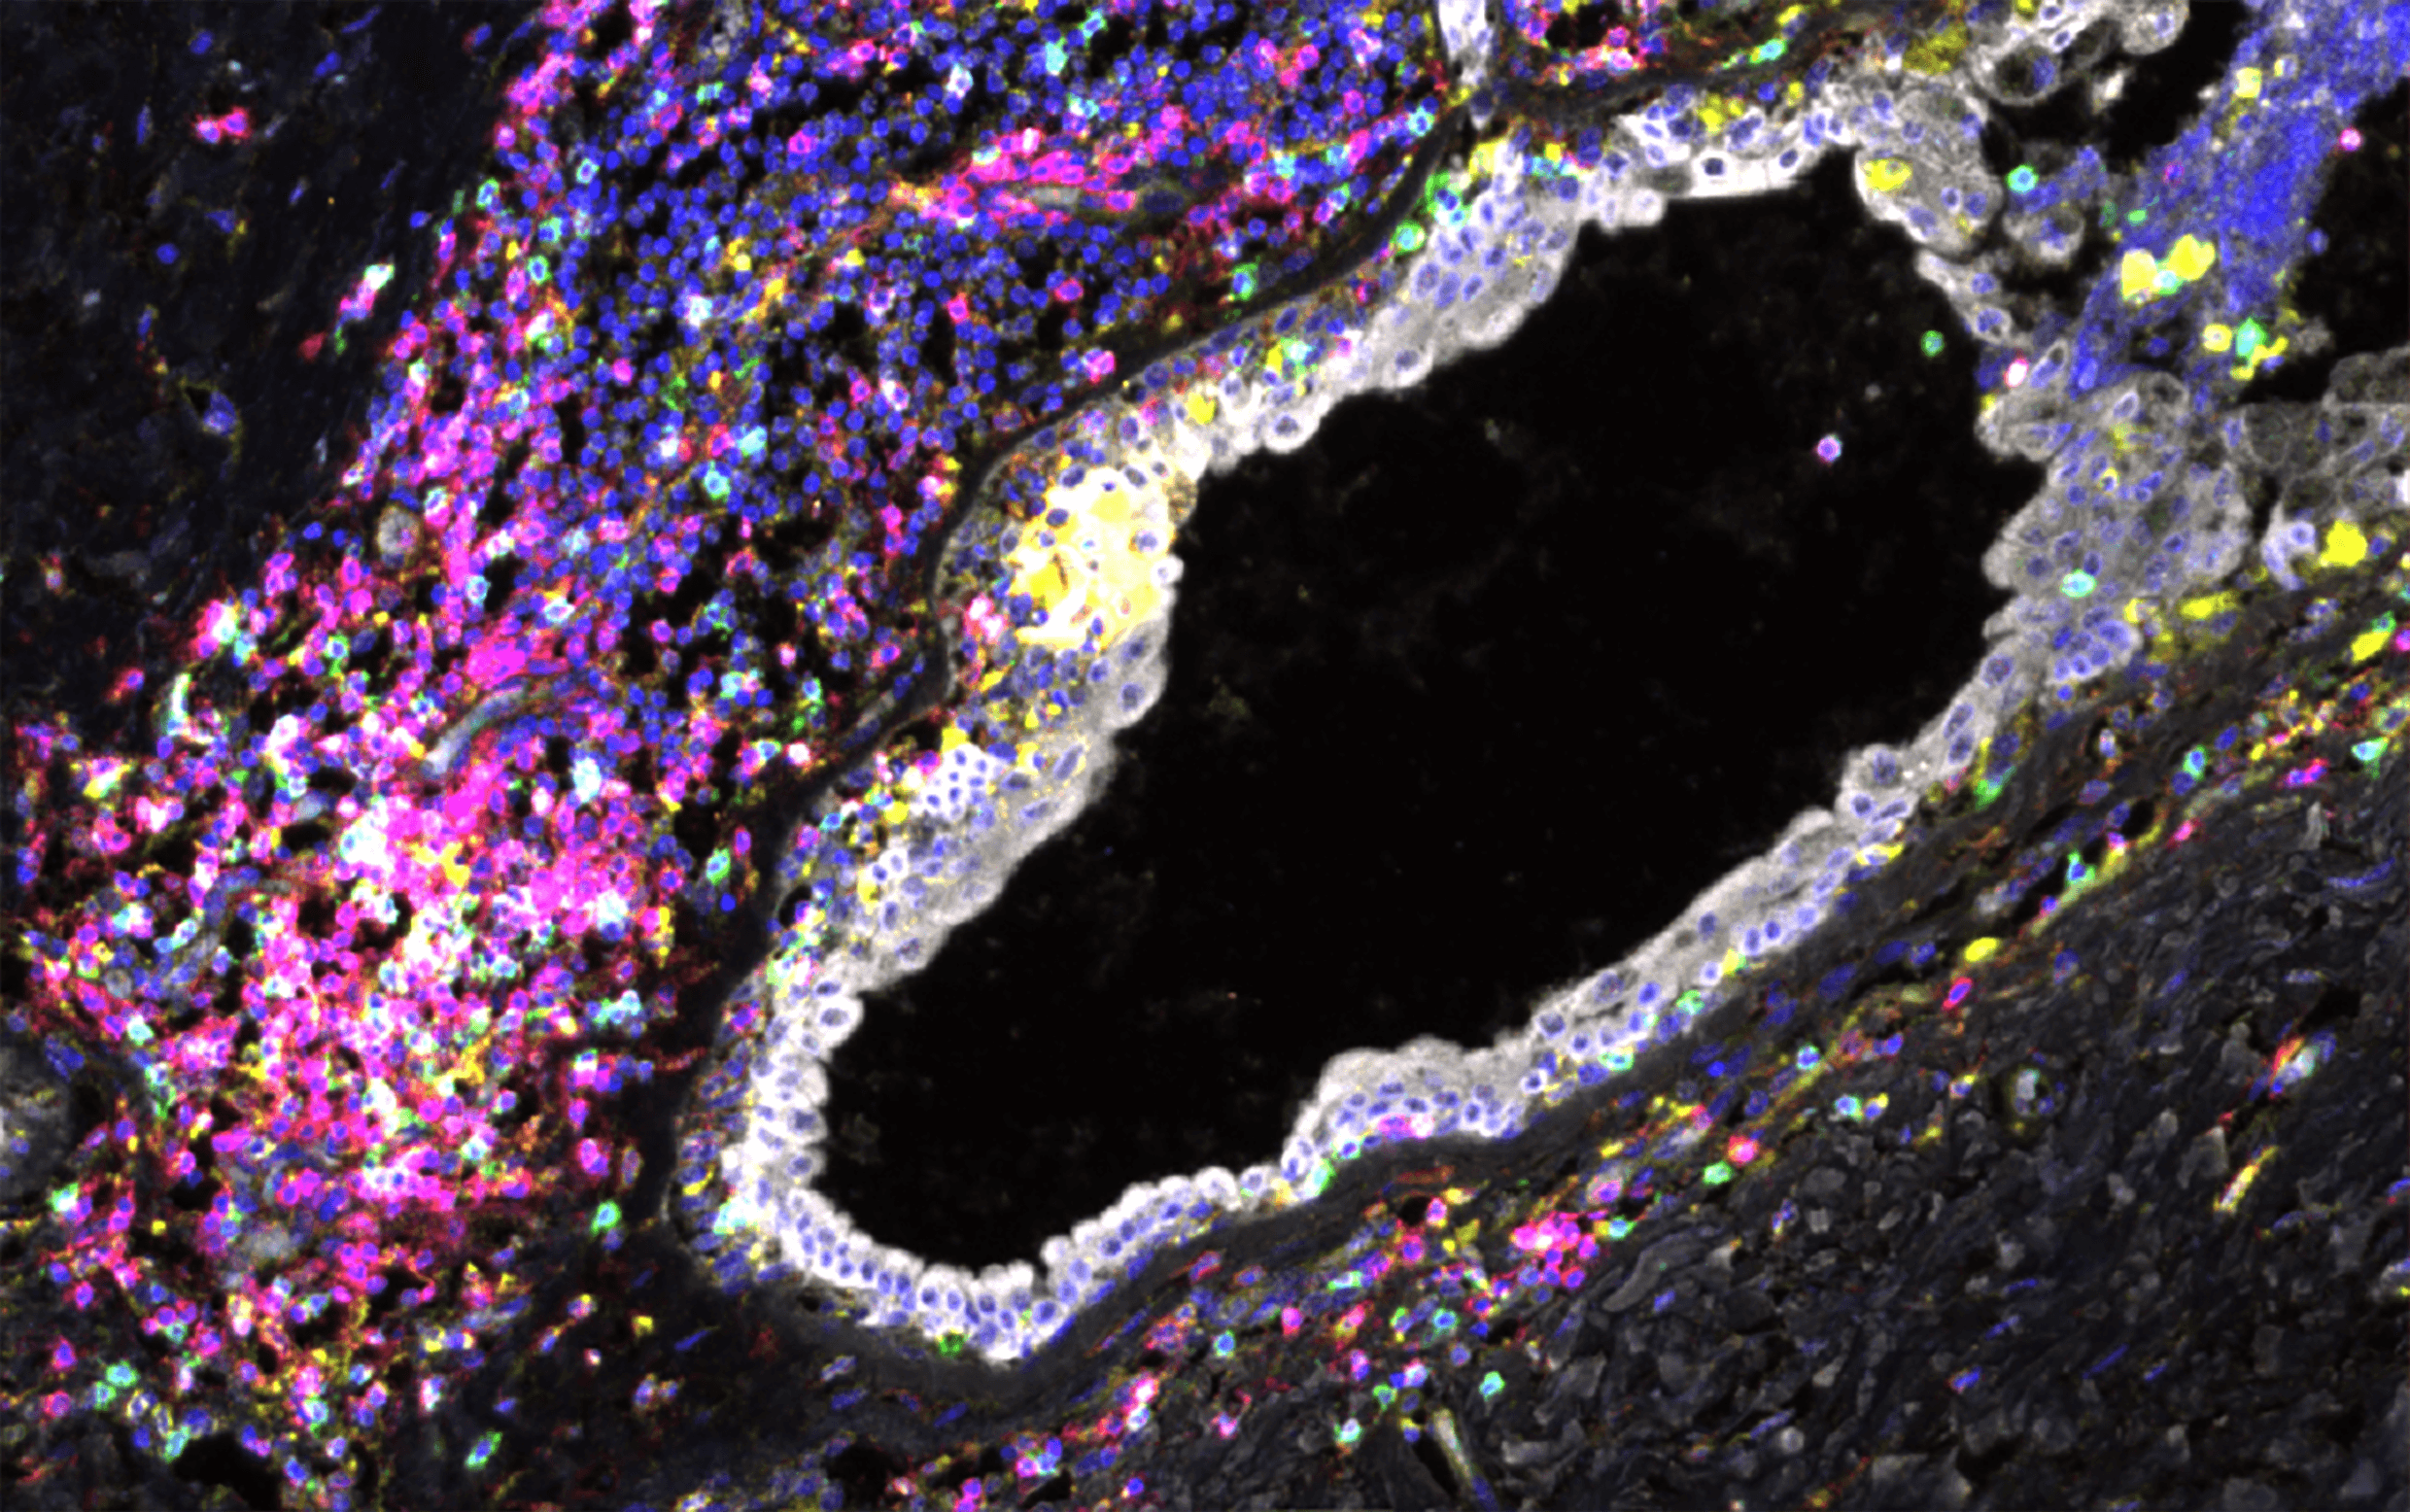

Project award

The project aims to build a high-resolution map of cellular and molecular transition along the breast tumour development. Using this map, the team wants to understand the impact of germline mutations on tumour initiation and disease progression.

Project leads: Walid Khaled, Hisham Mohammed

Collaborating institutions: University of Cambridge, OHSU